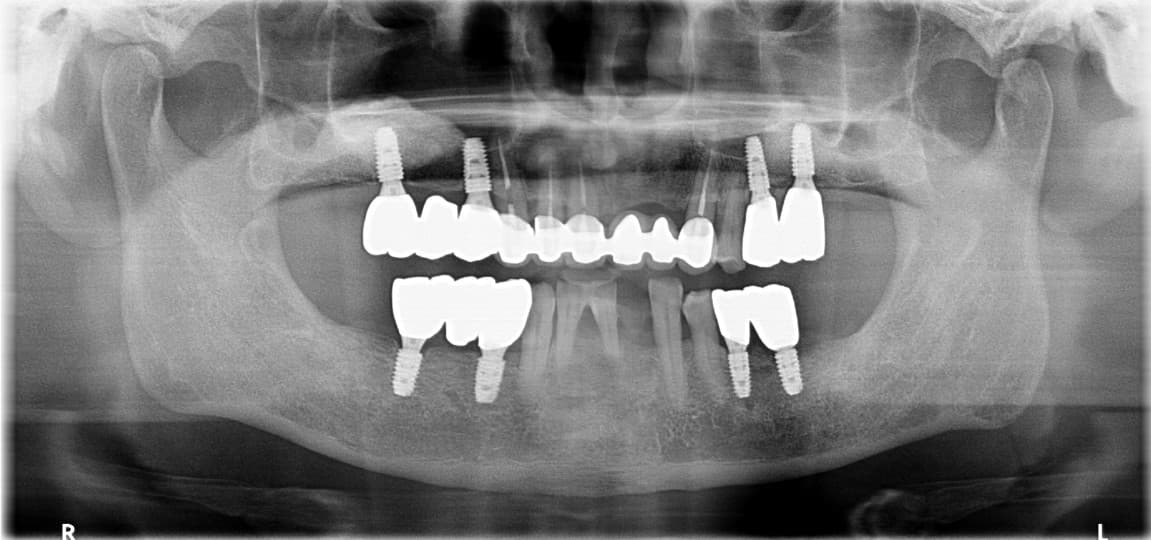

Minimal Implants

Just 6 upper and 4 lower implants for secure fixation